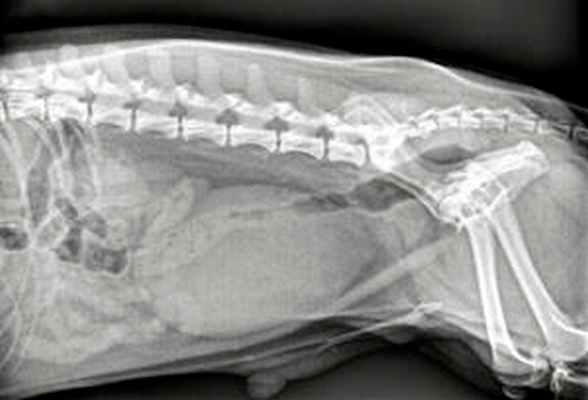

- для выявления повреждений опорно-двигательного аппарата, спинного или головного мозга пациент направляется на рентген, компьютерную томографию и МРТ-диагностику.

Дальнейший поиск повреждений позвоночника, спинного мозга включает в себя рентгенографию, миелографию, КТ и МРТ.